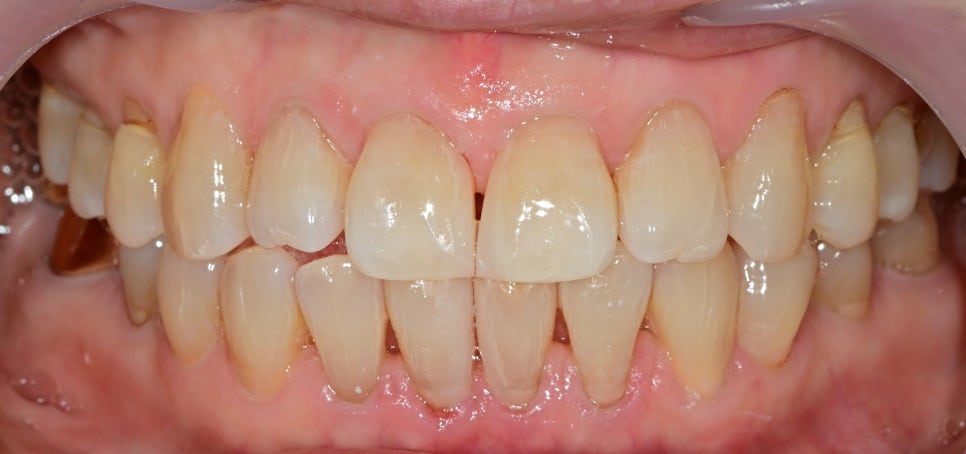

위아래 공간을 채운 후 사진입니다.

당연히 치아 삭제는 전혀 없었고,

레진을 이용한 빈 공간을 채웠습니다.

사실 환자분께서는

아래 공간은 위 공간에 비해 작게 벌어져서

치료를 고민하셨지만 치료 후

채워진 치아 사진을 보고 굉장히 만족하셨고

나중에 치아 형태나 색상을 변화시킬수 있는

전체적인 라미네이트에 대해서도

적극적으로 고민해 보시겠다고 하셨습니다.

작은 공간이지만

앞니 같은 경우는 치료 전후가 드라마틱 하게 달라지며

무의식적으로 웃는 모습까지 변화시켜 줍니다.

치아가 벌어져있었기 때문에 내려앉았던 잇몸은

시간이 지나며 빈 공간으로 채워 올라올 것이고

추후 체크를 통해 치아 색상이나 형태를 수정할 필요가 있습니다.